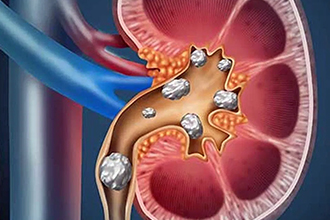

Stone disease occurs when chemicals in your urine become concentrated and form crystals in your urinary tract. It most often affects your kidneys, though it can also affect your bladder, the tubes that carry urine from your kidneys to your bladder (ureters), or the tube that connects your bladder to the outside of your body (urethra).